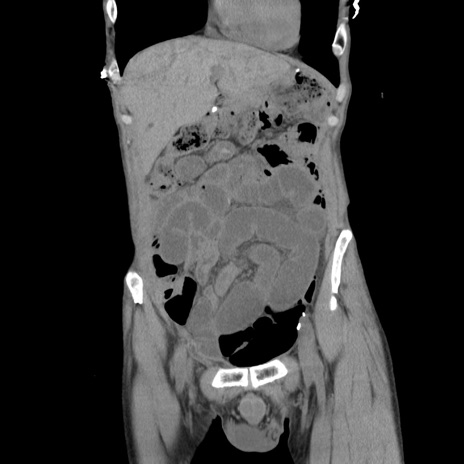

症例11(冠状断像)

【症例】 60歳代男性

【主訴】 下腹部痛

【現病歴】 本日夜中より下腹部痛の症状認め、受診。

【既往歴】 膀胱癌(膀胱全摘+尿管皮膚瘻術) 、胃癌術後

【身体所見】 BT 35.3℃、PR 58/min、BP 136/98mHg、腹部平坦、軟、腸蠕動音±、ストマ留置あり、左上腹部~正中部に圧痛あり、反跳痛なし。

【データ】WBC 5100、CRP0.01